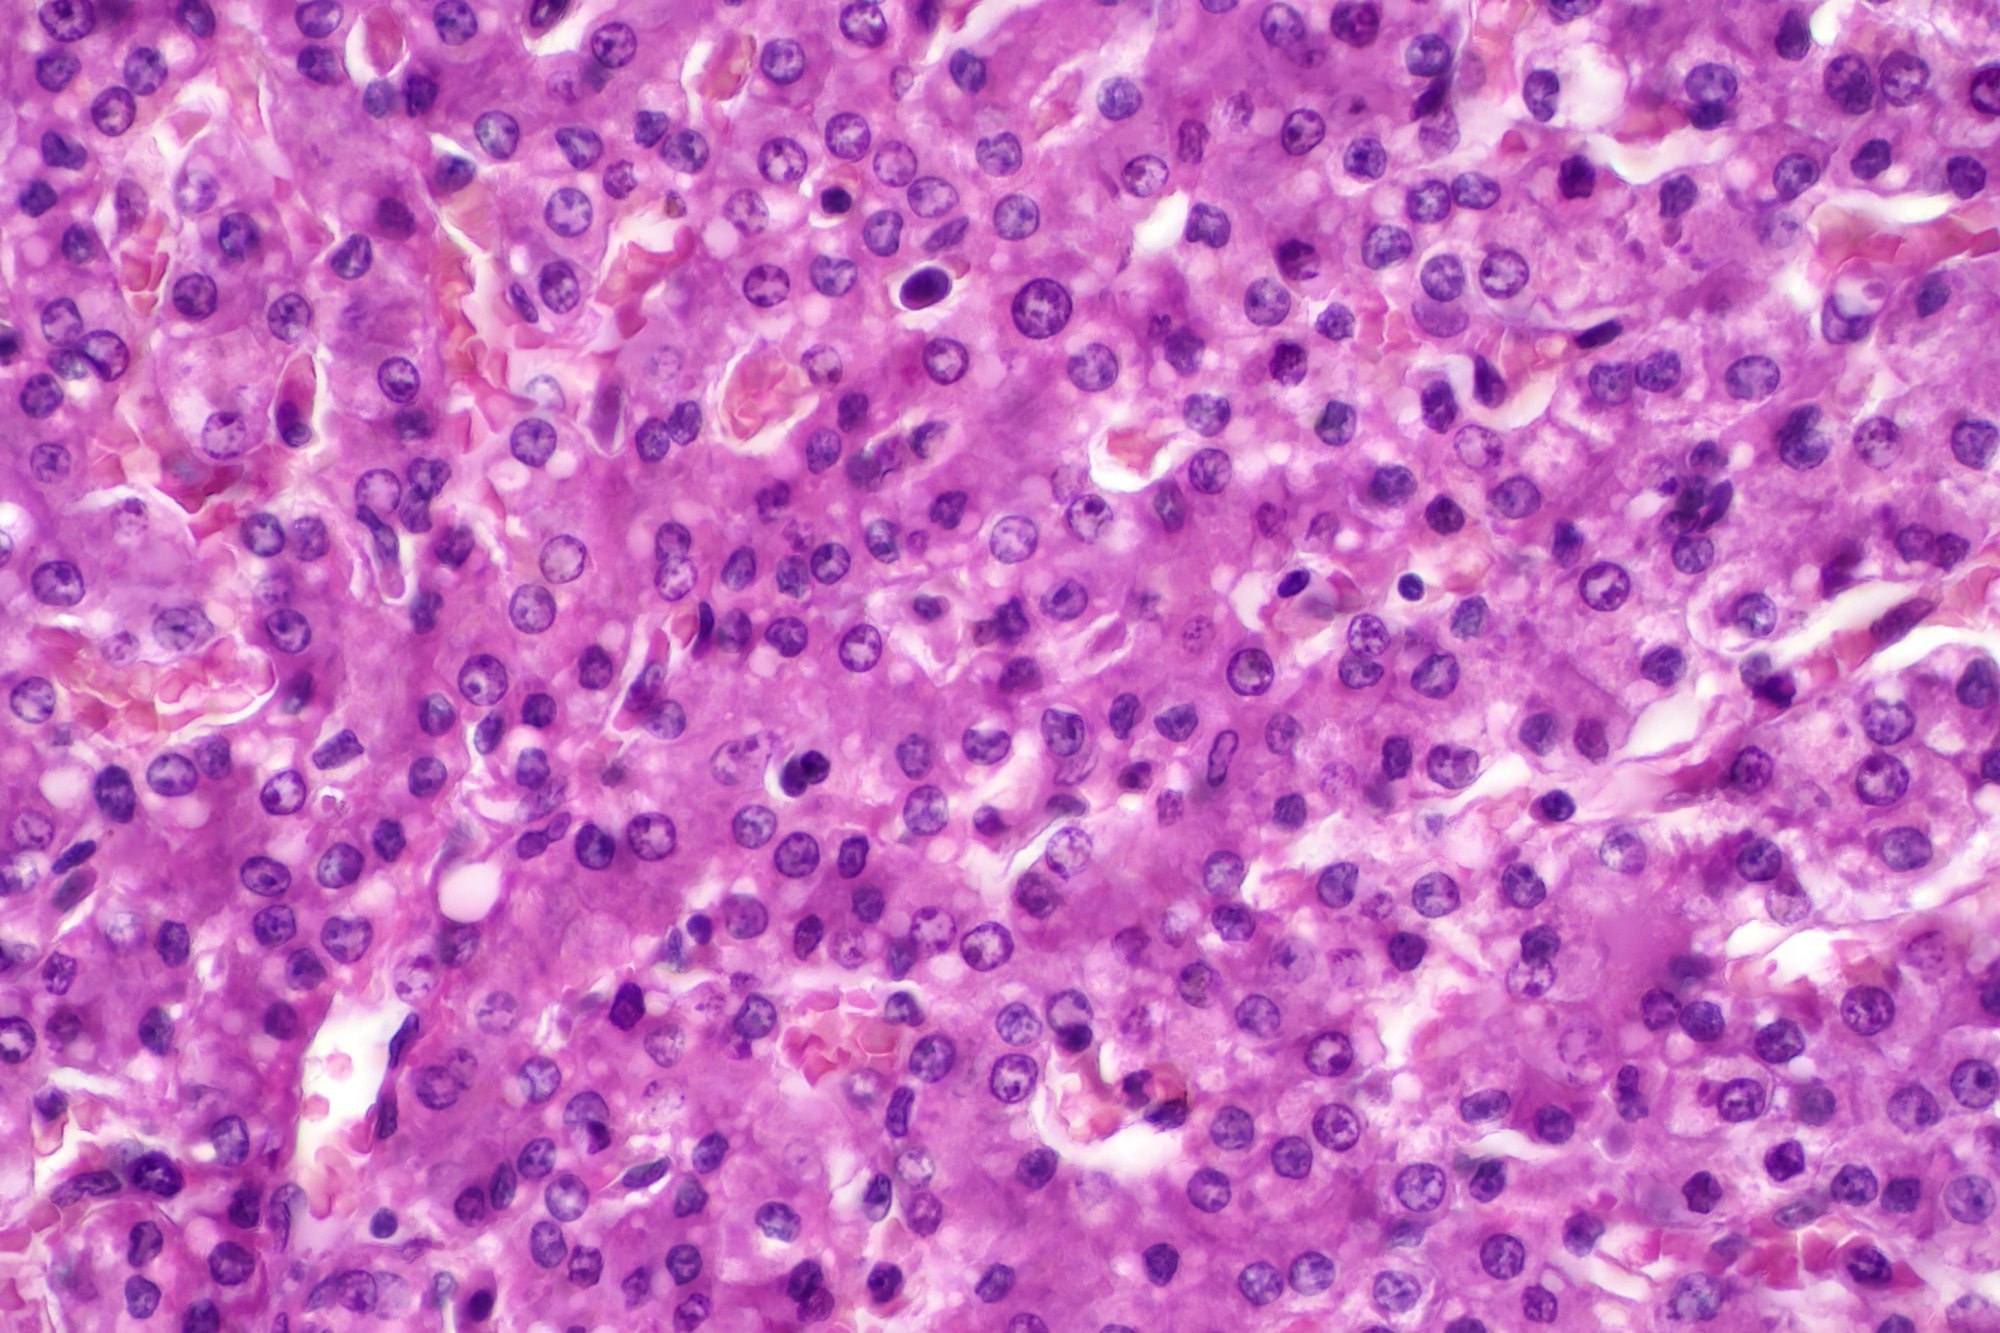

Organoids result image from the CellDrop FLi Automated Cell Counter.

Traditional automated cell counting algorithms are looking for either bright or dark objects that are small and round and stain evenly against the background. These algorithms do great with tissue culture cells or many types of primary cells, especially when using fluorescence. In contrast, hepatocytes and organoids are irregularly shaped with many internal structures and tend to be grown in complex environments with many other objects, such as debris or other cell types. Since these samples have a lot of internal structure or, in the case of organoids, many dozens or hundreds of cells per object, it is difficult to get even staining. These factors combine to make these sample types nearly impossible to count accurately using traditional cell counting algorithms.